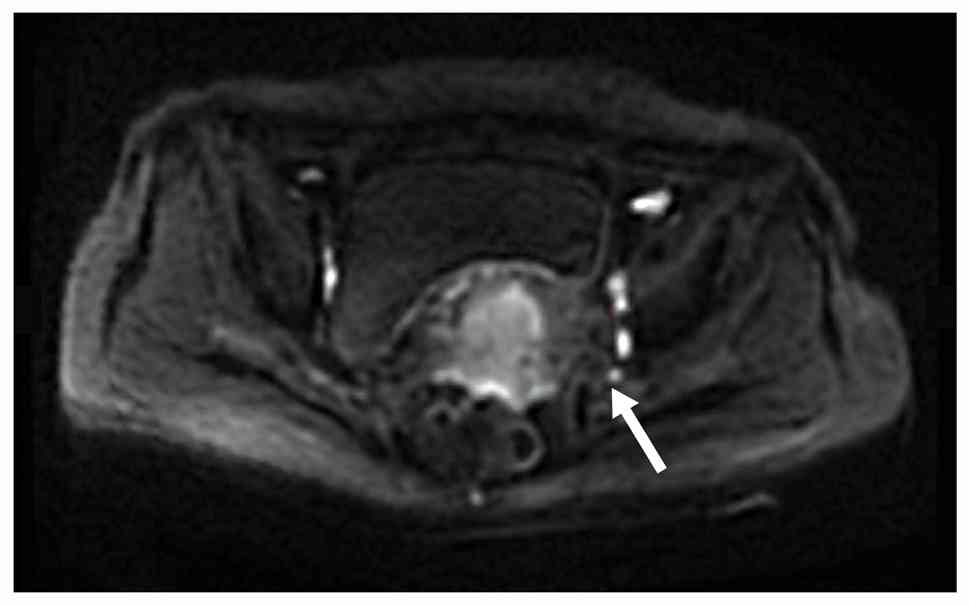

Examples of MRI diagnostic images from multiple patients are shown in Fig. 1, Fig. 2, Fig. 3, Fig. 4, Fig. 5. Fig. 1 shows an irregular soft-tissue mass in the cervical region, clearly visible on the axial sequence of T2-weighted fat-saturated imaging. The mass may suggest cervical lesions or tumors. Fig. 2 displays multiple lymph node metastases in the pelvic region on the axial sequence of DWI. The high-signal areas indicate that the lymph nodes might be affected by tumor metastasis. Fig. 3 reveals an irregular soft-tissue mass in the cervical region on the sagittal sequence of T2-weighted fat-saturated imaging. The mass is shown to have extended into the vaginal area, with the sagittal view aiding in the assessment of the lesion's longitudinal extent. Fig. 4 displays an irregular soft-tissue mass in the cervical region on T1-weighted enhanced imaging. The mass shows significant heterogeneous enhancement, suggesting that the lesion may be malignant. Fig. 5 illustrates a lesion in the cervical and vaginal regions on the sagittal sequence of T1-weighted enhanced imaging. The lesion area demonstrates heterogeneous enhancement, further indicating the possibility of a malignant tumor.

T1-weighted enhanced imaging showing

an irregular soft-tissue mass (white arrow) in the cervical region,

with notable heterogeneous enhancement.

Figure 4.

T1-weighted enhanced imaging showing an irregular soft-tissue mass (white arrow) in the cervical region, with notable heterogeneous enhancement.